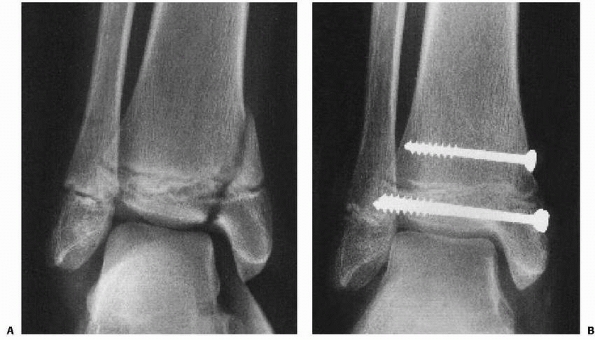

![]() |

FIGURE 26-2

Comminuted Salter-Harris type IV fracture of the distal tibia and displaced Salter-Harris type I fracture of the distal fibula produced by an inversion (shearing) mechanism in a 10-year-old girl. |

fracture of the tibia produced by a shearing (Fig. 26-2)

or crushing force might be more likely to result in growth arrest than